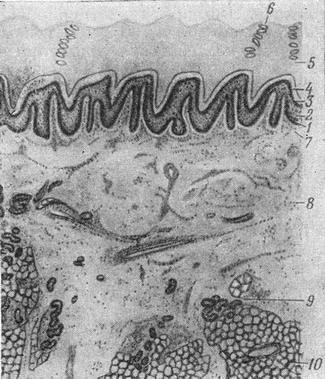

![]() Рис. 1.будова шкіри пальця людини: 1 - 5 - епідерміс (1 - базальний шар; 2 - шиповидный шар; 3 - зернистий шар; 4 - блискучий шар; 5 - роговий шар); 6 - вивідна протока потової залози; 7 і 8 - дерма (7 - сосочковий шар; 8 - сітчастий шар); 9 - кінцевий відділ потової залози; 10 - жирова тканина. |

Будова шкіри. У шкірі розрізняють два відділи: верхній - епітеліальний (епідерміс) і нижній - сполучнотканинний (власне шкіра - дерма). Межа між епідермісом і дермою представляється у вигляді нерівній хвилястої лінії внаслідок наявності на поверхні дерми особливих виростів, так званих шкірних сосочків (рис. 1).

Епідерміс складається з п'яти шарів клітин. Шар епідермісу, розташований безпосередньо на кордоні з дермою, носить назву основного базального шару. Він складається з одного ряду клітин, роз'єднаних вузькими щілиноподібними канальцями і з'єднуються між собою протоплазматическими відростками. Клітин базального шару притаманні дві особливості: 1) вони постійно розмножуються і шляхом диференціювання утворюють клітини верхніх шарів; 2) у цих клітинах утворюється, а також міститься пігмент меланін.

Другий шар носить назву шилоподібного. Він складається з декількох рядів неправильної форми клітин зі світлим ядром, також роз'єднаних щілиноподібними канальцями. Третій шар носить назву зернистого: він складається з одного-двох рядів подовжених, витягнутих клітин, що тісно прилягають один до одного.

8 протоплазмі їх знаходяться зерна кератогиаліна, що є першим етапом утворення рогової речовини. Четвертий шар носить назву блискучого. Він виявляється тільки на ділянках з товстим епідермісом (долоні, підошви), має вигляд блискучої смужки, що складається з сплощені без'ядерних клітин, і є наступним етапом в утворенні рогового речовини. Останнім, верхнім шаром епітелію є роговий шар, складається з тонких без'ядерних клітин, тісно з'єднаних між собою і містять особливу білкова речовина кератин. У самої зовнішньої частини роговий шар менш компактний, окремі пластинки відстають один від одного обумовлюючи постійне фізіологічне відходження віджилих епітеліальних елементів. Товщина епідермісу і, зокрема, його рогового шару на різних ділянках шкіра неоднакова. Найбільш потужний він на долонях і підошвах, значно тонше на бічних поверхнях тулуба, особливо тонкий на століттях і зовнішніх статевих органах чоловіків.

Дерма - сполучнотканинна частина шкіри, складається з двох шарів: подэпителиального, так званого сосочкового і сітчастого. Сосочковий шар побудований з нежноволокнистой сполучної тканини, що складається з тонких пучків колагенових, еластичних і аргірофільних (ретикулиновых) волокон. Останні на кордоні з епітелієм разом з проміжним речовиною утворюють так звану базальну мембрану, яка відіграє велику роль в обмінних процесах між епітелієм і дермою. Колагенові волокна сосочкового шару поступово переходять у більш товсті пучки сітчастого шару і утворюють тут густе сплетіння з великою кількістю еластичних волокон. У сітчастому і сосочковом шарах містяться різні клітинні елементи (фібробласти, гістіоцити, огрядні клітини та ін); серед сполучнотканинних волокон закладені невеликі пучки гладких м'язів, пов'язаних з волосяними фолікулами.

Товсті пучки колагенових волокон сітчастого шару переходять безпосередньо в підшкірну жирову клітковину, де утворюють широку мережу, петлі якої заповнені жировими клітинами. Жирова клітковина обумовлює рухоме прикріплення шкіри до підлягає тканин і оберігає її від механічних пошкоджень і розривів.